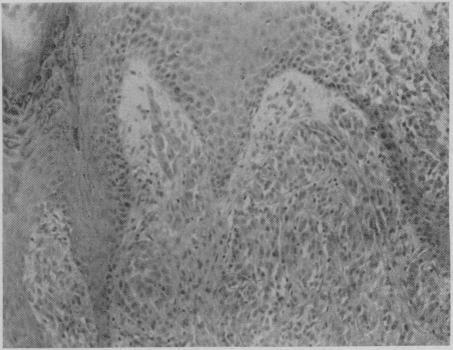

Histopathology of malignant melanomas and certain benign tumours of melanocytic origin.

Can Med Assoc J. 1968 Jul 6;99(1):7-10.